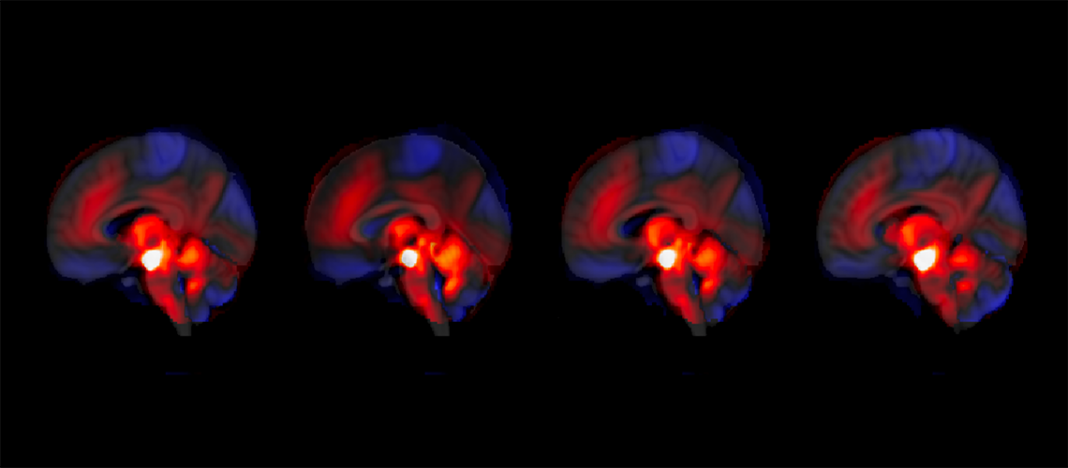

Une équipe de l’Université de Genève et des Hôpitaux Universitaires de Genève a découvert un rôle inattendu du cervelet dans la modulation des symptômes négatifs de la schizophrénie, tels que l’apathie, le retrait social et la perte de motivation. Ces symptômes, qui sont parmi les plus invalidants et difficiles à traiter, sont liés à des anomalies du système de récompense cérébral, notamment une suractivation de l’aire tegmentale ventrale (ATV) productrice de dopamine. L’étude révèle que le cervelet, traditionnellement associé à des fonctions motrices, joue également un rôle crucial dans la régulation émotionnelle et cognitive, influençant ainsi le système de récompense.

L’étude a suivi 146 patients sur une période de 3 à 9 mois et a utilisé une cohorte indépendante pour validation. Les chercheurs ont observé que le cervelet interagit avec l’ATV, et une régulation renforcée de cette interaction est associée à une atténuation des symptômes négatifs. Cette découverte ouvre la voie à des approches thérapeutiques non invasives, telles que la stimulation magnétique transcrânienne, qui pourrait cibler le cervelet pour moduler son influence sur l’ATV. Un essai clinique randomisé est en cours pour évaluer l’efficacité de cette méthode.